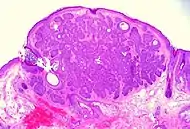

Trichoblastoma | Absence of cleft, rudimentary hair germs, papillary mesenchymal bodies. | ![]() |